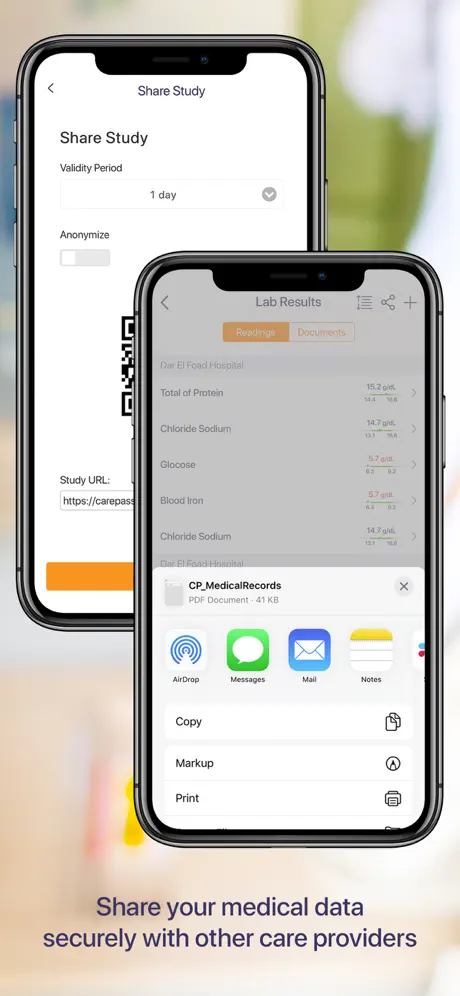

- Conectar y compartir los estudios radiológicos de forma segura con sus proveedores de atención

- Conectar y compartir los estudios radiológicos de forma segura con sus proveedores de atención